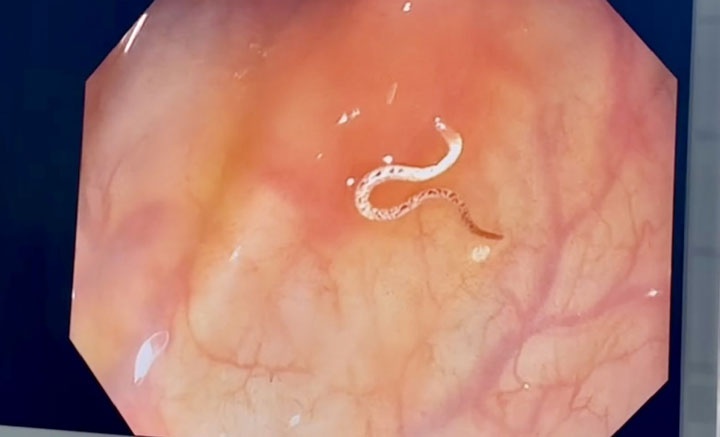

Sau khi vào bụng, ê-kíp phẫu thuật thấy có hơn 100 ml mủ đục rất hôi, mạc nối lớn và đại tràng dính vào tử cung với nhiều giả mạc. Sau khi ê-kíp gỡ dính, thấy tử cung có vết rách ngang 5 cm và vết rách xuống 3 cm ngay vị trí vết mổ.

Vùng hố chậu trái của người bệnh có khối áp xe to, đại tràng sigma và mạc nối dính thành một khối và dính vào thành bụng. Ê-kíp tiến hành cắt tử cung, gỡ các khối dính, kiểm tra đại tràng không thấy tổn thương, rửa sạch bụng, lấy hết giả mạc.